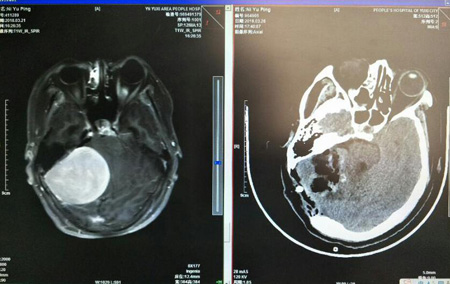

神外一科经过CT、MRI检查及仔细询问情况后,诊断该患者为颅内巨大肿瘤,肿瘤位于患者后颅窝右侧小脑桥脑角,是一个脑膜瘤。肿瘤大小约有成年男子拳头大小,且血供极为丰富,手术切除难度较大。

术前、术后患者CT检查对比